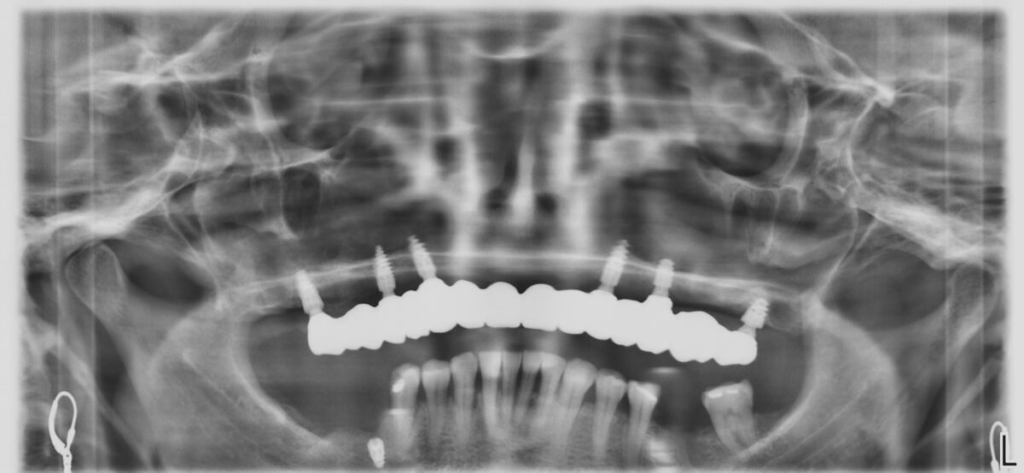

- CBCT 3D, vyšetření, fotodokumentace

- 4–6 implantátů metodou All-on-X

Technika All-on-X — I. fáze

Technika All-on-X — II. fáze